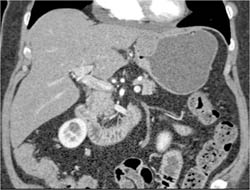

GIST Tumor